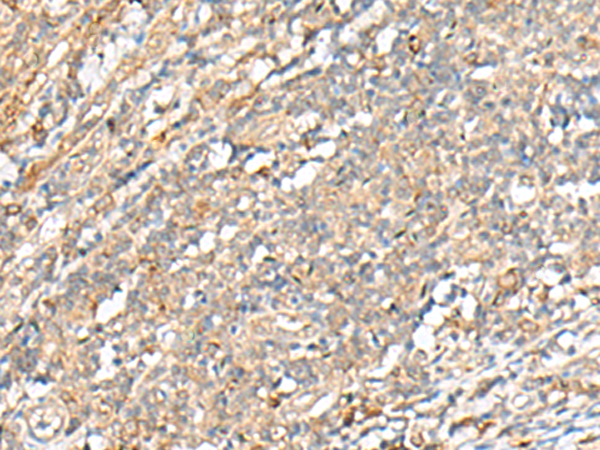

分类: 科研抗体货号: P09976别名: TIC; EFA6B应用: IHC反应种属: Human, Mouse